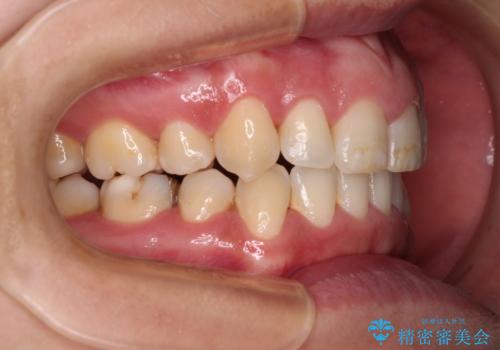

- 上下前歯のデコボコを気にして来院された患者様です。

デコボコが強いため、非抜歯で矯正をすると出っ歯仕上がりとなるため、上下左右の第一小臼歯4本を抜歯することとしました。